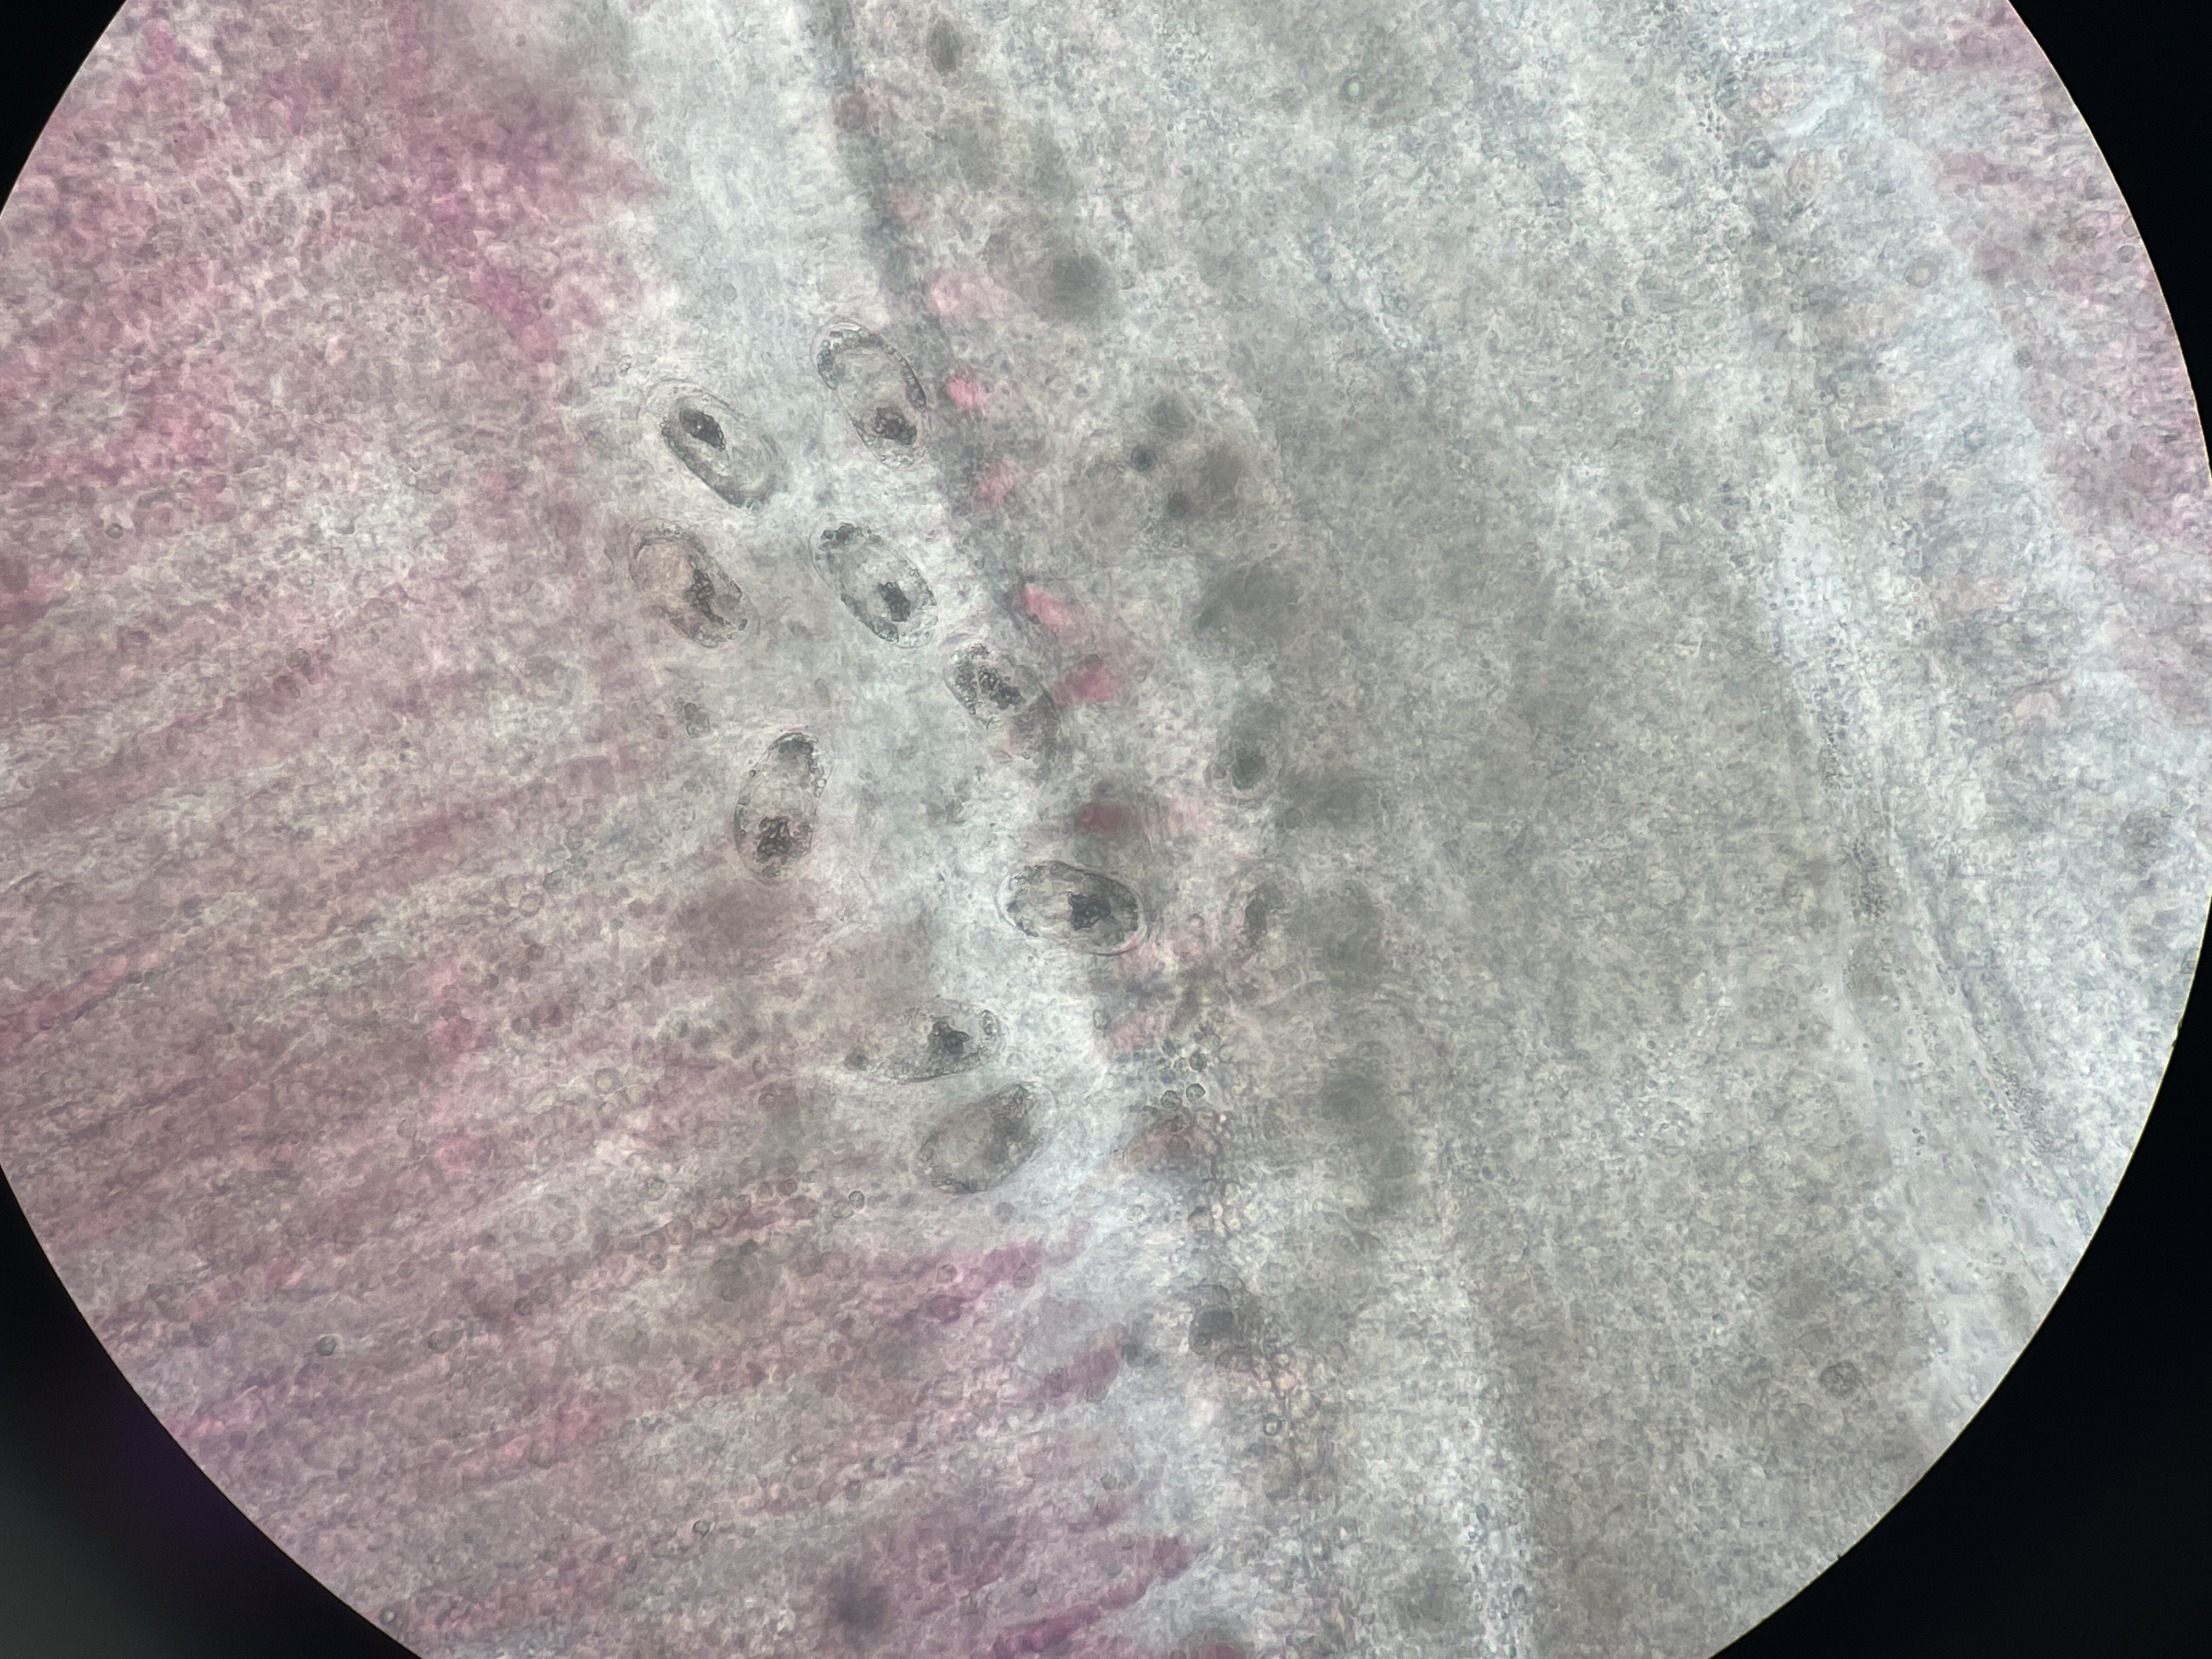

Microsporidiosi digestiva

Agente: Enterospora nucleophila (Enterocytozoonidae, parassita Microsporodiano).

Sintomi: Il protozoo intranucleare risiede all'interno dei nuclei degli enterociti e delle cellule rodlet nel tratto digestivo dell'orata. I pesci colpiti mostrano deperimento e grave anemia.

Appare durante l'inverno, ma la malattia può diventare più grave quando le temperature aumentano.

Controllo: Nessun trattamento. La prevenzione consiste nella separazione di pesci di diverse dimensioni per ridurre la trasmissione.